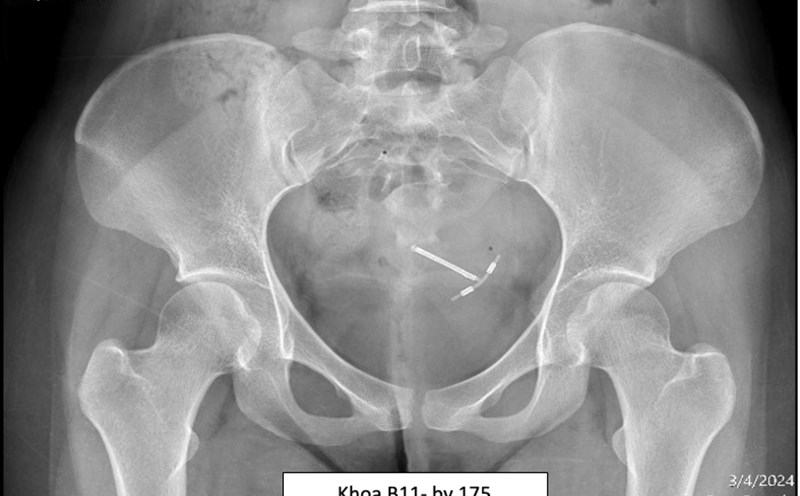

Lấy vòng tránh thai lạc trong ổ bụng, đâm xuyên tử cung của 2 phụ nữ

NGUYỄN LY |

TPHCM - Vừa qua, Bệnh viện Quân y 175 đã thực hiện phẫu thuật nội soi lấy vòng tránh thai lạc chỗ trong ổ bụng cho 2 nữ bệnh nhân.